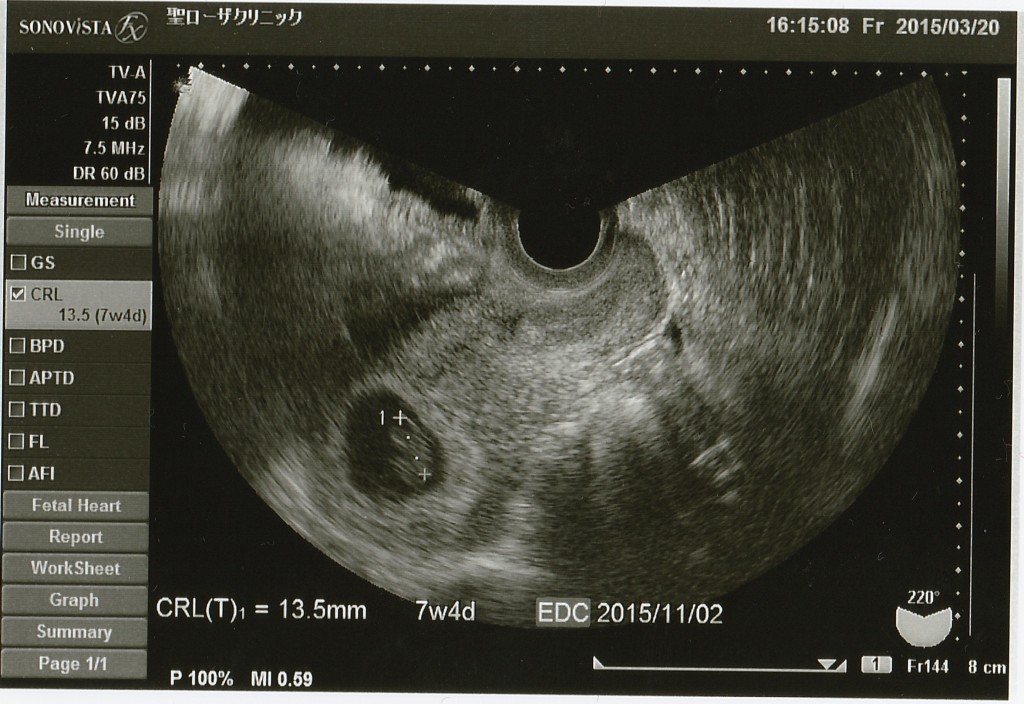

妊娠週数 ずれてる- 回答一覧 排卵するのも着床するのも1・2週間ならずれることありますよー^^ その前に、その日に受精したとは限らないので 私は体外受精でしたが、採卵した日と戻した日から数えても出産予定日は思っていた日より1週間くらいずれてました。 7mmから15.7mmに大きくなっていれば順調に育ってると思いますよ。 2週間後に心拍確認できるといいですね ズレていれば妊娠週数を修正し更に分娩予定日も修正する必要があります ※CRL赤ちゃんの頭からお尻までの大きさ ですが 1週間程度のズレなら 最終月経からの予定日の算出のままにして修正はしません 第2子がそうだったんですが 最終月経からみてCRLが小さかったのですが 1週間程度のズレでしたので 予定日を修正せずにいったら